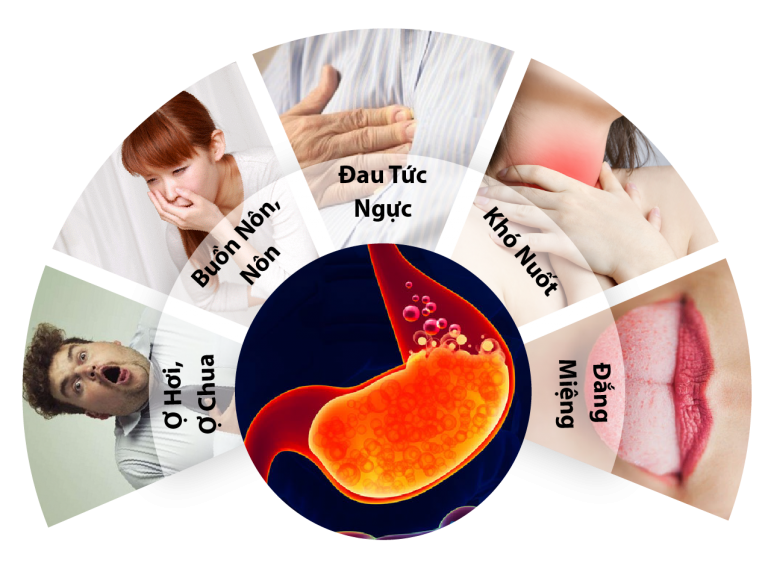

Buồn nôn và nôn: Có thể do tác động của các chất độc lên dạ dày và dấu hiệu của việc các chất thải không được loại bỏ qua thận.